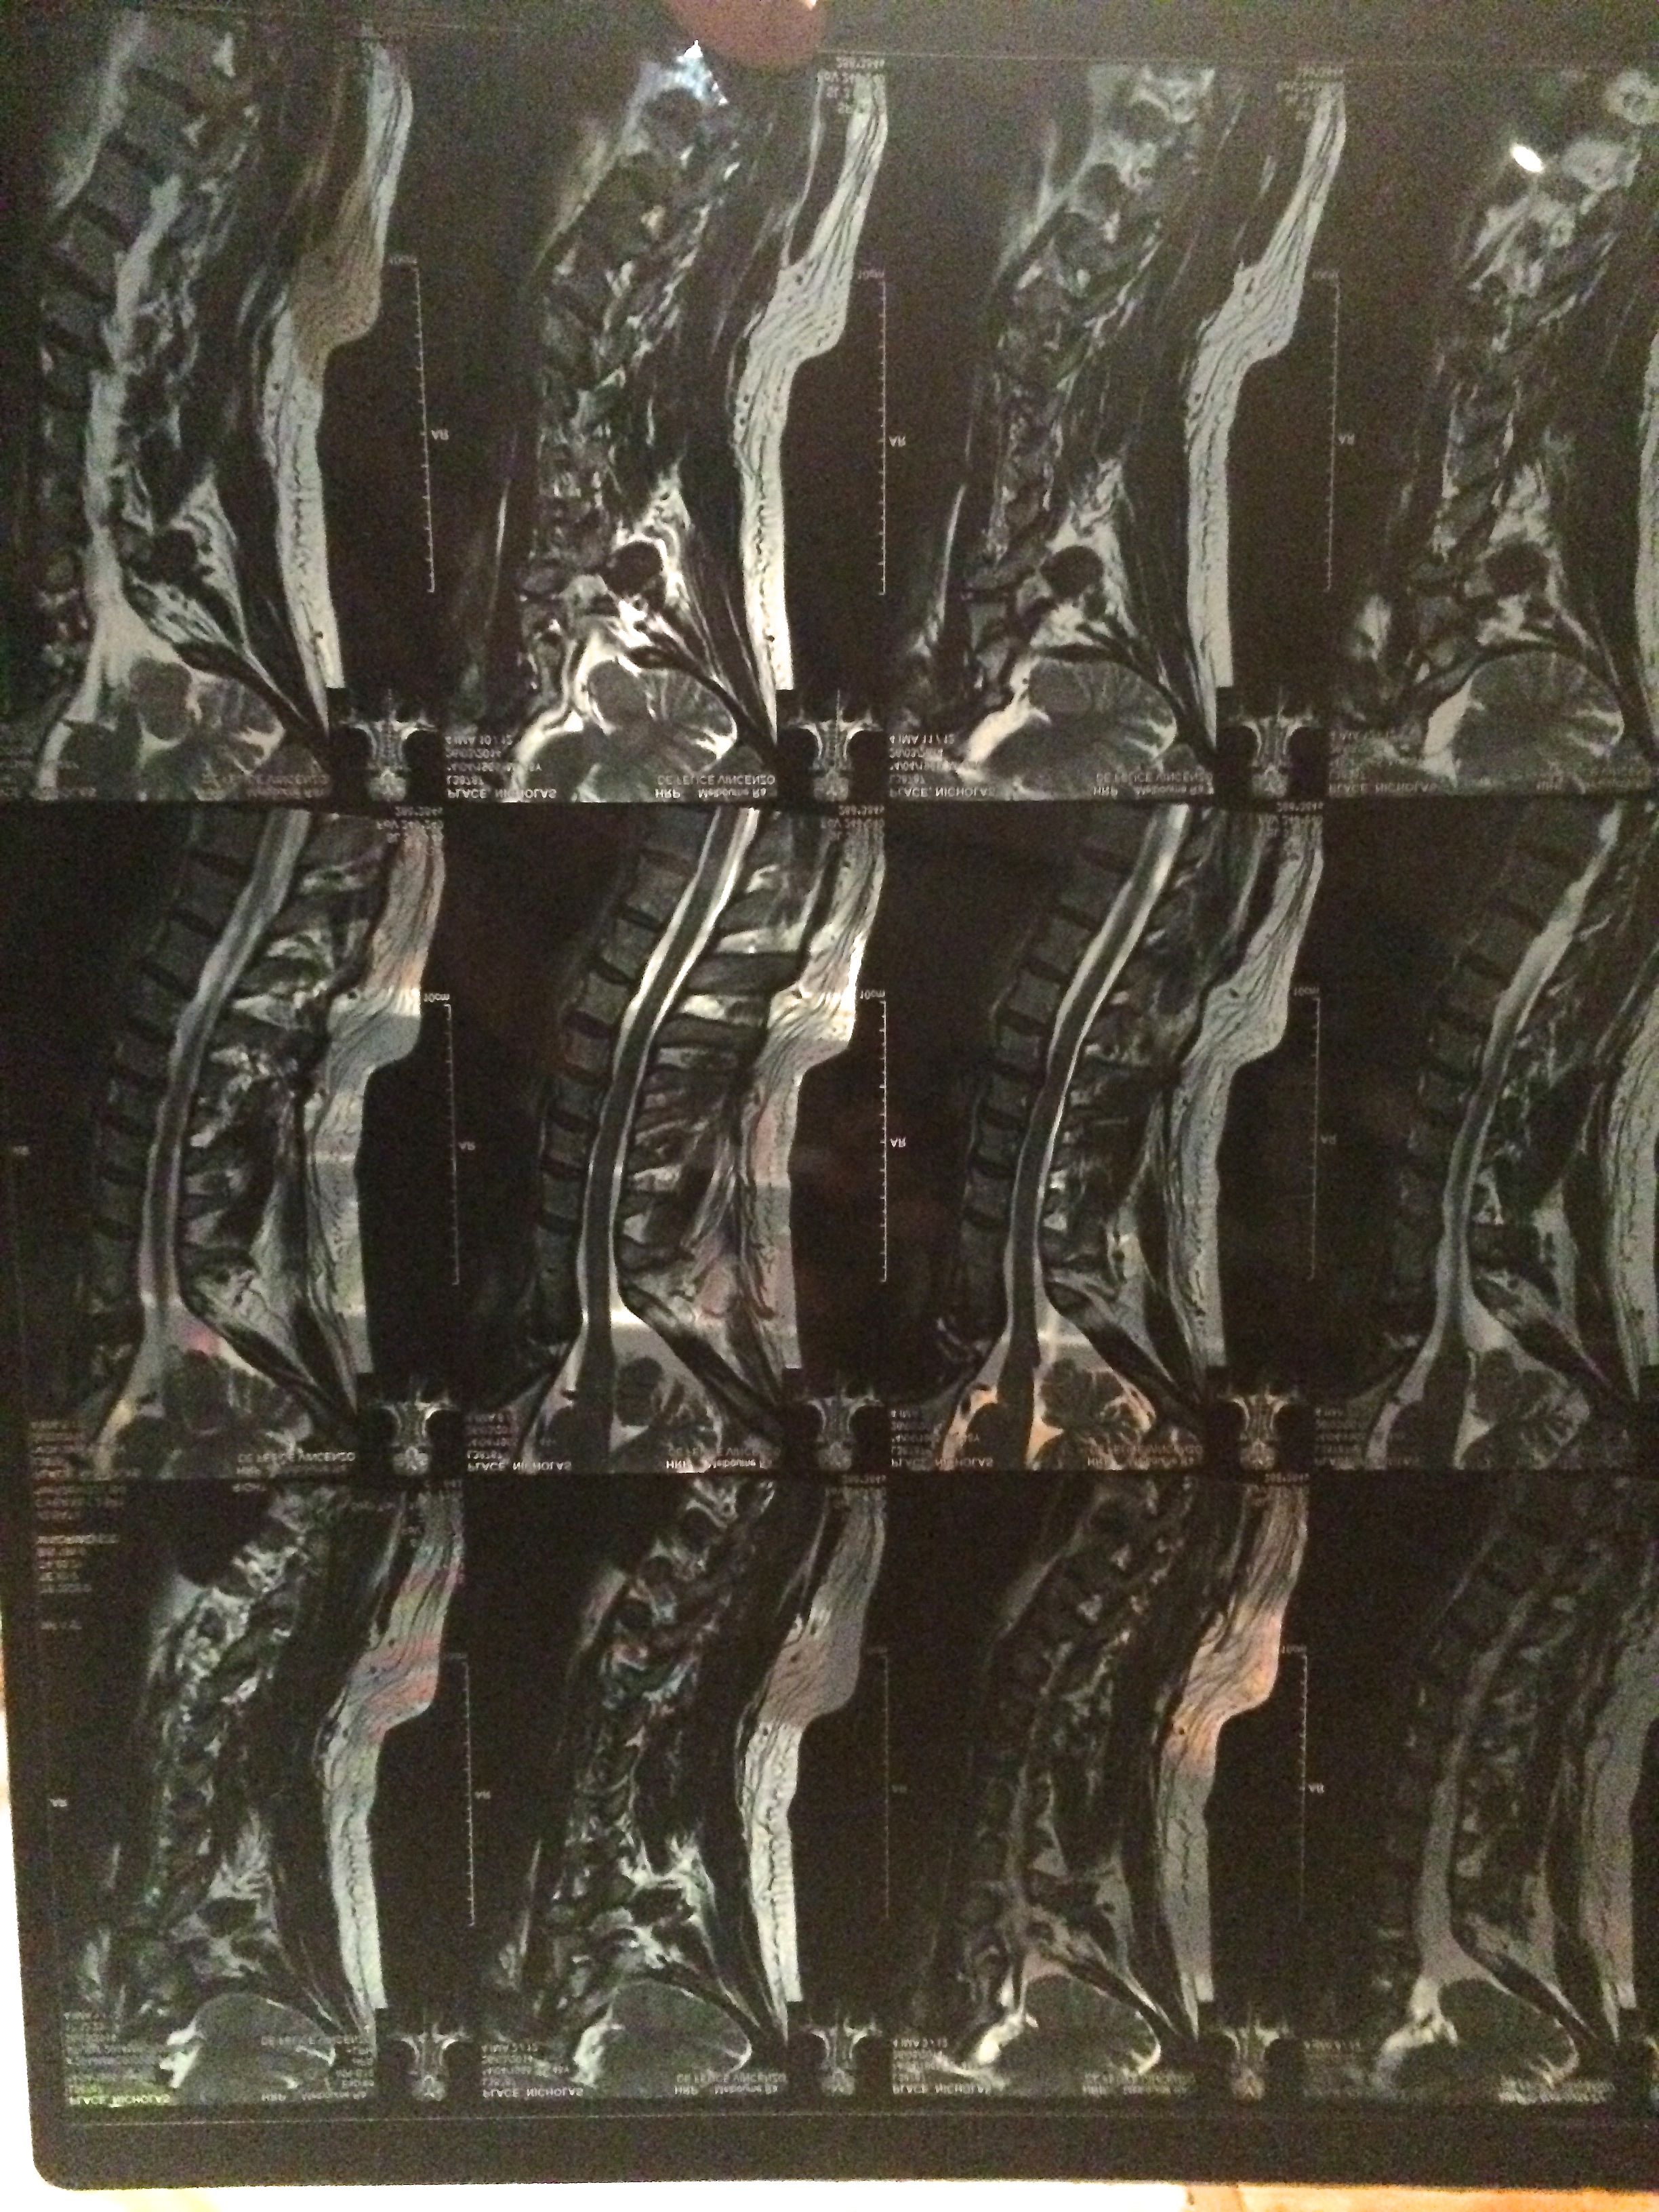

But lately I’ve been dealing with a nasty neck injury, which I have barely mentioned on the blog because I was so sick of whingeing about my busted knee for months. I went and saw the osteo, Magic Enzo, yesterday, armed with some MRI results, and he said the good news was that I didn’t have a tumor messing things up in the nerves around my spine, but it did look a lot like I’d hurt my neck in a car crash. Except I don’t think I’ve been in a car crash severe enough to cause that damage, or a hockey collision huge enough to compare. But apparently, somewhere along the way, I have hurt myself that badly without noticing.